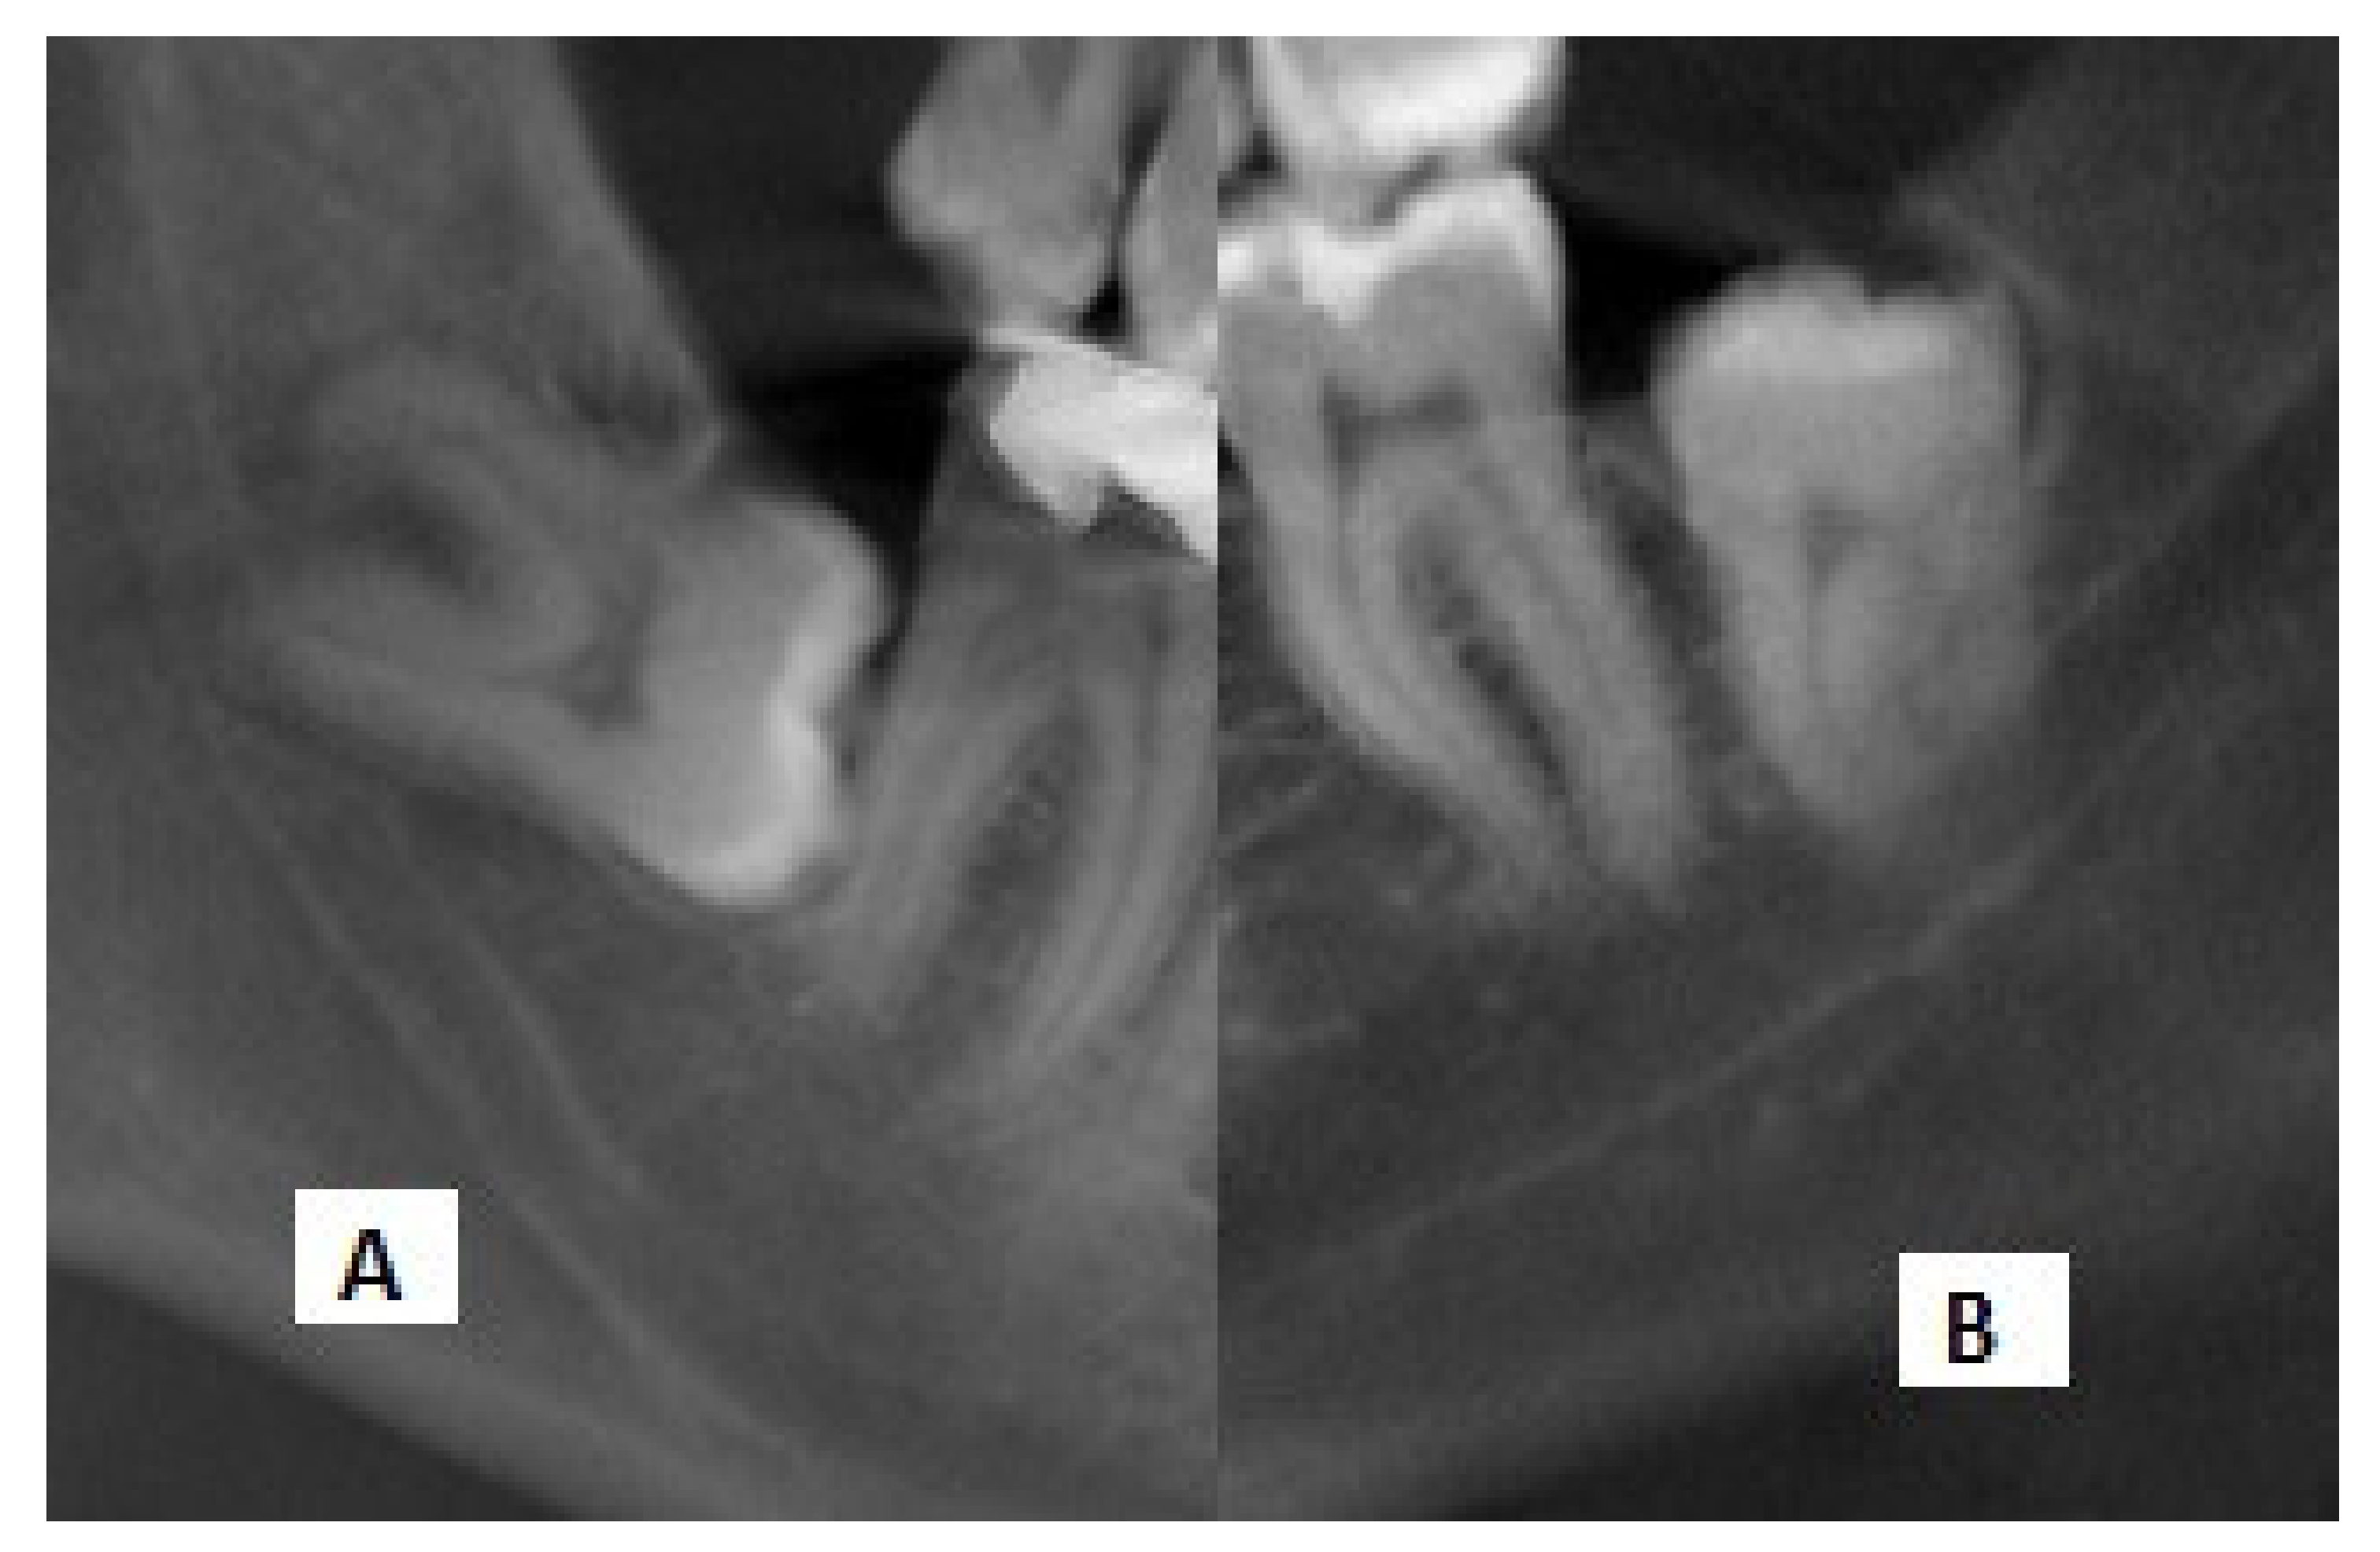

There are seven radiographic signs that are regarded as risk factors for the contact of the IMTMs with the MC on panoramic images, according to the classification by Rood and Shehab: namely (I) root darkening, (II) root deflection, (III) root narrowing, (IV) darkening and branching of the root, (V) interference with the white line, (VI) MC diversion, and (VII) MC narrowing [11] (Figure 1). Evidence shows that interference with the white line of the MC is the most common panoramic radiographic finding, which indicates direct contact of the two structures and is associated with a high risk of nerve damage and paresthesia [12]. Moreover, root darkening is among the strongest signs for the prediction of IAN exposure and paresthesia [13].

Figure 1. Seven radiographic signs for the contact of the IMTMs with the MC on panoramic images, based on the classification by Rood and Shehab: (A) root darkening, (B) root deflection, (C) root narrowing, (D) darkening and branching of the root, (E) interference with the white line, (F) MC diversion, and (G) MC narrowing.